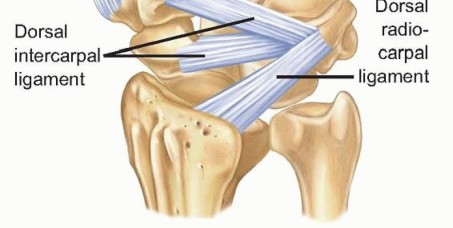

The trapezium and triquetrum similarly possess specialized anatomical features that dictate their fracture patterns and surgical management. The trapezium features a prominent volar ridge, which, akin to the hamate hook, serves as the radial attachment for the transverse carpal ligament. Medial to this ridge lies a deep fibro-osseous groove that houses the flexor carpi radialis (FCR) tendon. Fractures of the trapezial ridge can lead to painful FCR tendinopathy or rupture. The triquetrum, situated on the ulnar aspect of the proximal row, is heavily tethered by the dorsal radiocarpal and dorsal intercarpal ligaments. Extreme wrist flexion and ulnar deviation can cause these robust ligaments to avulse a fragment of the dorsal triquetral cortex, resulting in the most common non-scaphoid carpal fracture. Understanding these specific ligamentous and tendinous associations is critical for interpreting fracture displacement and planning surgical approaches.

The surgical approach to the capitate is predominantly dorsal, given its central location and the risk of injury to palmar vascular structures. A longitudinal dorsal incision is centered over the third metacarpal base, extending proximally towards Lister's tubercle. The extensor retinaculum is incised, typically developing an interval between the third (extensor pollicis longus) and fourth (extensor digitorum communis) extensor compartments. The tendons are carefully retracted, and the posterior interosseous nerve (PIN) is identified and protected, or prophylactically neurectomized to denervate the dorsal capsule and reduce postoperative pain. A ligament-sparing dorsal capsulotomy—often a ligament-splitting or a flap-based approach preserving the dorsal intercarpal and radiocarpal ligaments—is performed to expose the midcarpal joint.

Triquetral body fractures, while less common than dorsal avulsions, demand rigid fixation when displaced to restore the integrity of the proximal row. A dorsal longitudinal approach is utilized, entering between the fourth and fifth extensor compartments. The dorsal radioulnar and radiocarpal ligaments are incised to expose the triquetrum. Following reduction, fixation is typically achieved with small headless compression screws or multiple K-wires. Conversely, the ubiquitous dorsal triquetral avulsion fractures are almost universally managed non-operatively with a short period of immobilization. Surgical excision of the avulsed fragment is reserved strictly for cases of recalcitrant, chronic dorsal ulnar-sided wrist pain that fails months of conservative therapy.